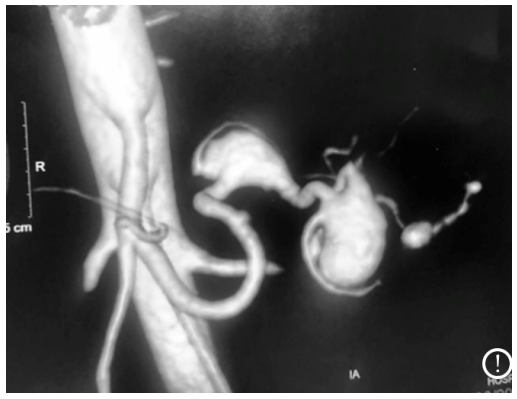

A imagem acima mostra parte de um exame com contraste arterial do abdômen superior. Com relação a ela, assinale a alternativa correta.